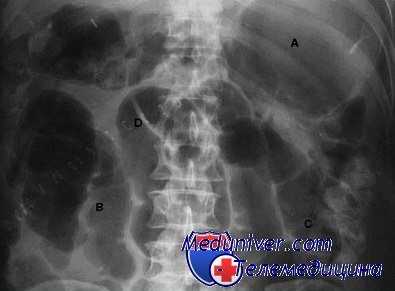

Неспособность вашего пациента принимать пищу, отсутствие отхождения газов или опорожнения кишечника в течение 5 дней после лапаротомии означает длительный послеоперационный илеус. Живот обычно вздут и «молчит» при аускультации. Обзорная рентгенография брюшной полости показывает значительно растянутые газами петли как тонкой, так и толстой кишки.

1. Рентгенологическое исследование

Признаки спаечной кишечной непроходимости при изучении пассажа водной взвеси бария сульфата по кишечнику:

- появление горизонтальных уровней жидкости при отсутствии арок (симптом "горизонтальных уровней"), которые придают “объемность” изображению (симптом "растянутой пружины");

- задержка бариевой взвеси в отдельных тонкокишечных петлях;

- симптом “провисания” кишечных петель, проявляющийся опусканием терминальных петель подвздошной кишки в нижние отделы брюшной полости и даже в полость малого таза.

Симптом “горизонтальных уровней” образуют разные контрастные среды, но не как обычно – воздух (арка) – жидкость, а только жидкость. Нижний уровень жидкости состоит из более тяжелой бариевой взвеси, верхний – из жидкости, появившейся в результате экссудации. Уровень жидкости без газа появляется на 2-4 часа раньше, указывая на уже наступившие микроциркуляторные нарушения.

Основной симптом спаечной кишечной непроходимости при рентгеноконтрастном исследовании – задержка водной взвеси бария сульфата в тонкой кишке дольше 4-5 часов.